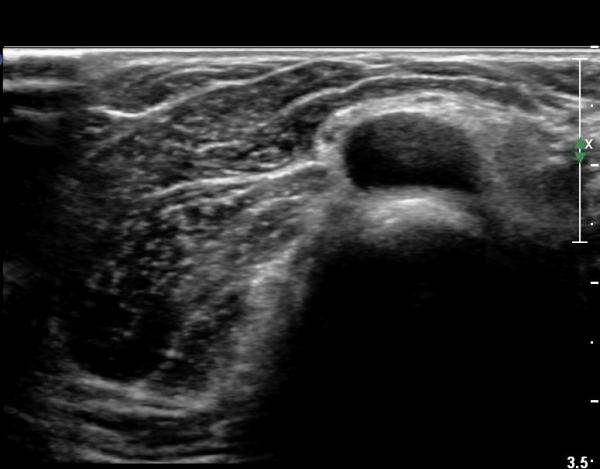

Á¶±Ý´õ ŽÃËÀÚ¸¦ ¸»´ÜÀ¸·Î À̵¿ÇÏ´Ï ³¶Á¾Àº ÀÛ¾ÆÁö°í ȸ¿Ü±Ù »çÀÌ¿¡ À§Ä¡ÇÏ´Â Èİñ°£ ½Å°æÀÇ

ºÎÁ¾ÀÌ °üÂûµÈ´Ù(»çÁø 6)

Èİñ°£ ½Å°æ Á¾´Ü¸é°Ë»ç¿¡¼­ ³¶Á¾¿¡ ÀÇÇÑ Èİñ°£ ½Å°æ ¾Ð¹Ú°ú  Èİñ°£ ½Å°æÀÇ ºÎÁ¾ÀÌ °üÂûµÈ´Ù(»çÁø 7).

out of plane À¸·Î ³¶Á¾ ÈíÀÎÀ» À§ÇØ ÁÖ»ç¹Ù´ÃÀÌ ³¶Á¾³»¿¡ À§Ä¡ÇÑ ¸ð½À(»çÁø 8)

³¶Á¾ ÈíÀÎ ÈÄ ³¶Á¾ÀÌ °ÅÀÇ º¸ÀÌÁö ¾Ê´Â ¸ð½À(»çÁø 9, 10)